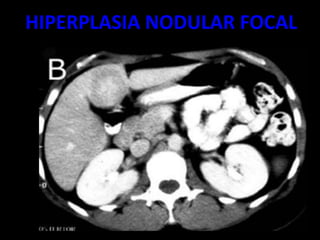

HIPERPLASIA NODULAR FOCAL